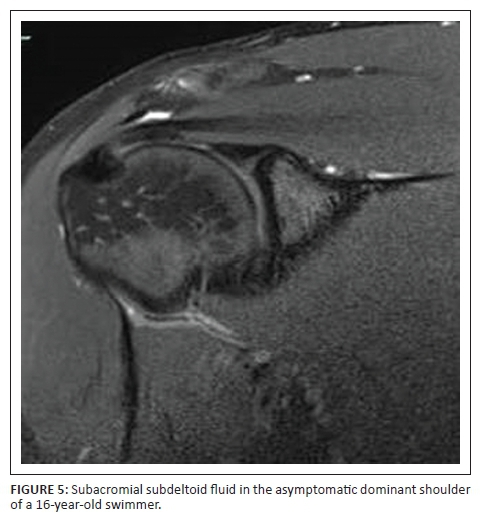

Of the 29 asymptomatic shoulders studied, 25 (86.2%) had MRI changes which could be viewed as abnormal. Ten (91%) of the 11 symptomatic shoulders had abnormal MRI findings. The most common MRI findings (Figures 1-3) in the symptomatic shoulders were supraspinatus partial tear (45.5% in symptomatic shoulders vs. 20.7% in asymptomatic shoulders), subacromial subdeltoid fluid (45.5% vs. 34.5%), increased signal in the AC Joint (45.5% vs. 37.9%), supraspinatus tendinosis (36.4% vs. 10.3%) and AC joint arthrosis (36.4% vs. 34.5%). Supraspinatus tendinosis (36.4% vs. 10.3%) and partial tear of the supraspinatus (45.5% vs. 20.7%) were much more common in the symptomatic shoulders compared with the asymptomatic shoulders. Biceps tendinosis was common in both symptomatic and asymptomatic shoulders (18.2% vs. 6.9%). Degeneration in the proximal bicipital groove (18.2% vs. 0%) was more common in the symptomatic population. Thickening of the inferior glenohumeral ligament was more common in the asymptomatic shoulders (13.8% vs. 0.0%). Increased signal of the labrum and labral tears were comparable in the two groups (10.0% vs. 10.3%).

Of the asymptomatic shoulders studied, 86.2% had MRI changes which could be viewed as abnormal. This corresponds to previous studies that showed that MRI abnormalities in asymptomatic overhead athletes are common.2,4,11 The most common findings in both the symptomatic and asymptomatic shoulders were subacromial subdeltoid fluid (Figure 5), increased signal at the AC joint (Figure 6), AC joint arthrosis, supraspinatus tendinosis (Figure 7) and biceps tendinosis (Figure 8). There were 11 symptomatic shoulders in our sample group with the most common clinical findings being impingement, AC joint tenderness, positive O' Brien's sign and biceps tenderness. The asymptomatic group also demonstrated positive clinical findings, with subacromial impingement, biceps tenderness and sternoclavicular tenderness being the most common findings. AC Joint tenderness was less common in the asymptomatic group. The studied group consisted of a slightly smaller symptomatic group than Sein et al., but our athletes more frequently demonstrated local AC joint tenderness and positive O'Brien's sign. Increased signal at the AC joint is a common finding in both the symptomatic and asymptomatic shoulders of overhead athletes and does not correlate with patient symptomatology as also noted in agreement with Reuter et al.12 In this study, type 1 acromion shape was most common followed by type 2 and type 3. There was no direct correlation between shoulder pain and acromion shape.

Supraspinatus tendinopathy was a common finding in both the symptomatic and asymptomatic shoulders, with it being nearly twice as common in the symptomatic shoulders. Previous studies also found supraspinatus tendinopathy to be a dominant finding.4 Biceps tendinosis was approximately twice as common in the symptomatic shoulder. Connor et al. showed that subacromial subdeltoid fluid was a common finding in the asymptomatic shoulder.6 This study demonstrated similar results with subacromial and/or subdeltoid fluid found in 34.5% of the asymptomatic shoulders. In a study where Reuter et al. evaluated shoulder MRI changes in 23 triathletes, 57% of the asymptomatic group and 31% of the symptomatic group demonstrated AC joint arthrosis.12 The current study demonstrated nearly equal percentages of AC joint arthrosis (36.4% symptomatic vs. 34.5% asymptomatic).